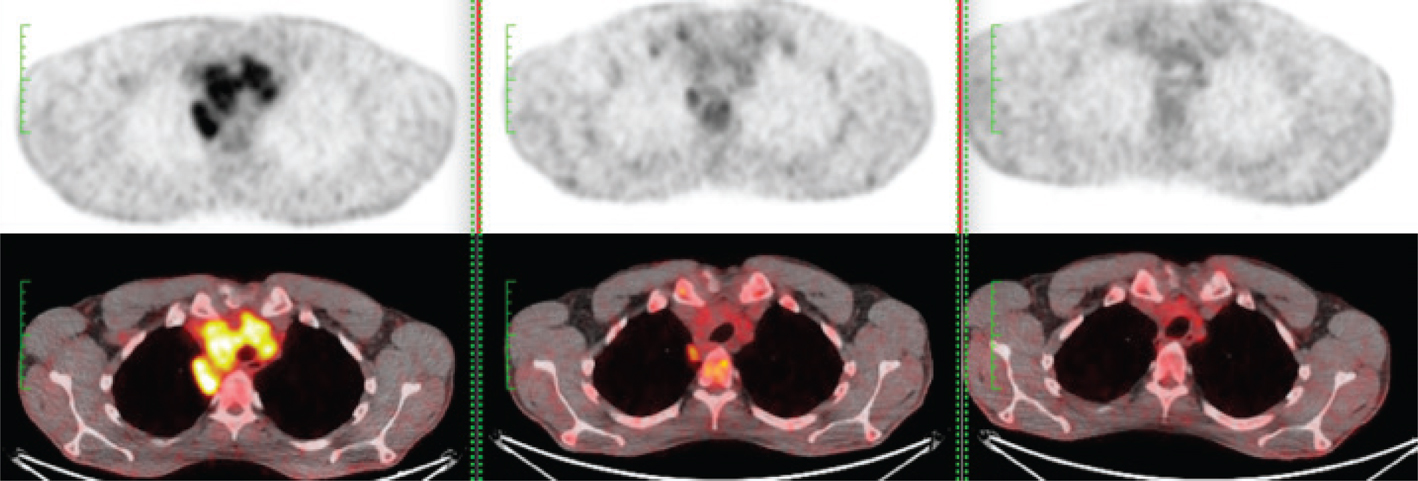

The histological diagnosis of FL is made according to the Saudi Lymphoma Group’s Clinical Practice Guidelines for Diagnosis, Management and Follow-up (34,40). Briefly, histological grading is made according to the the presence of centroblast (cB) per high-power field (HPF): grade 1 (0-5 cB per HPF), grade 2 (6-15 cB per HPF), grade 3A (>15 cB per HPF, cB with intermingled centrocytes), and grade 3B (>15 cB per HPF, pure sheets of blasts) (34). An example of different histology in FL patient is shown in Figure 3. The modern hybrid imaging diagnostic modality with PET/CT in a single-shot scan (41) is the recommended diagnostic tool to detect nodal and extranodal disease (1,42). Moreover, a PET/CT is essential to plan involved-site radiotherapy (ISRT) (43). An example of PET/CT before and after treatment in a FL patient is shown in Figure 4.

Fig 3

Figure 3. Histology of follicular lymphoma. The WHO Classification utilizes a I-III grading system based on increased numbers of centroblasts counted per high-power field. Grade I-II FL have 0 to 15 centroblasts (follicular mixed). A, Grade III FL has more than 15 centroblasts (follicular large cell). Grade III has been subdivided into grade IIIa, in which centrocytes are present, (B) and grade IIIb (C), in which there are sheets of centroblasts (Images courtesy of Saeed Shieban).